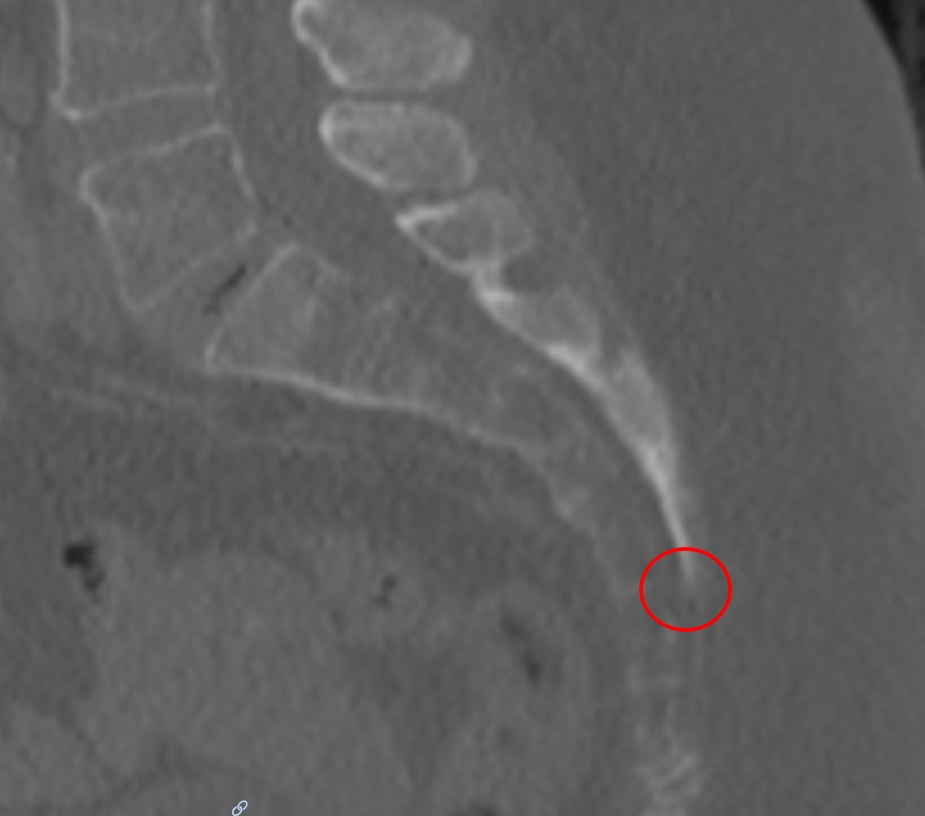

Hiatus sacralis im CT

Darstellung des Hiatus sacralis (roter Kreis) des Os sacrum in einer sagittalen CT Aufnahme im Knochenfenster.